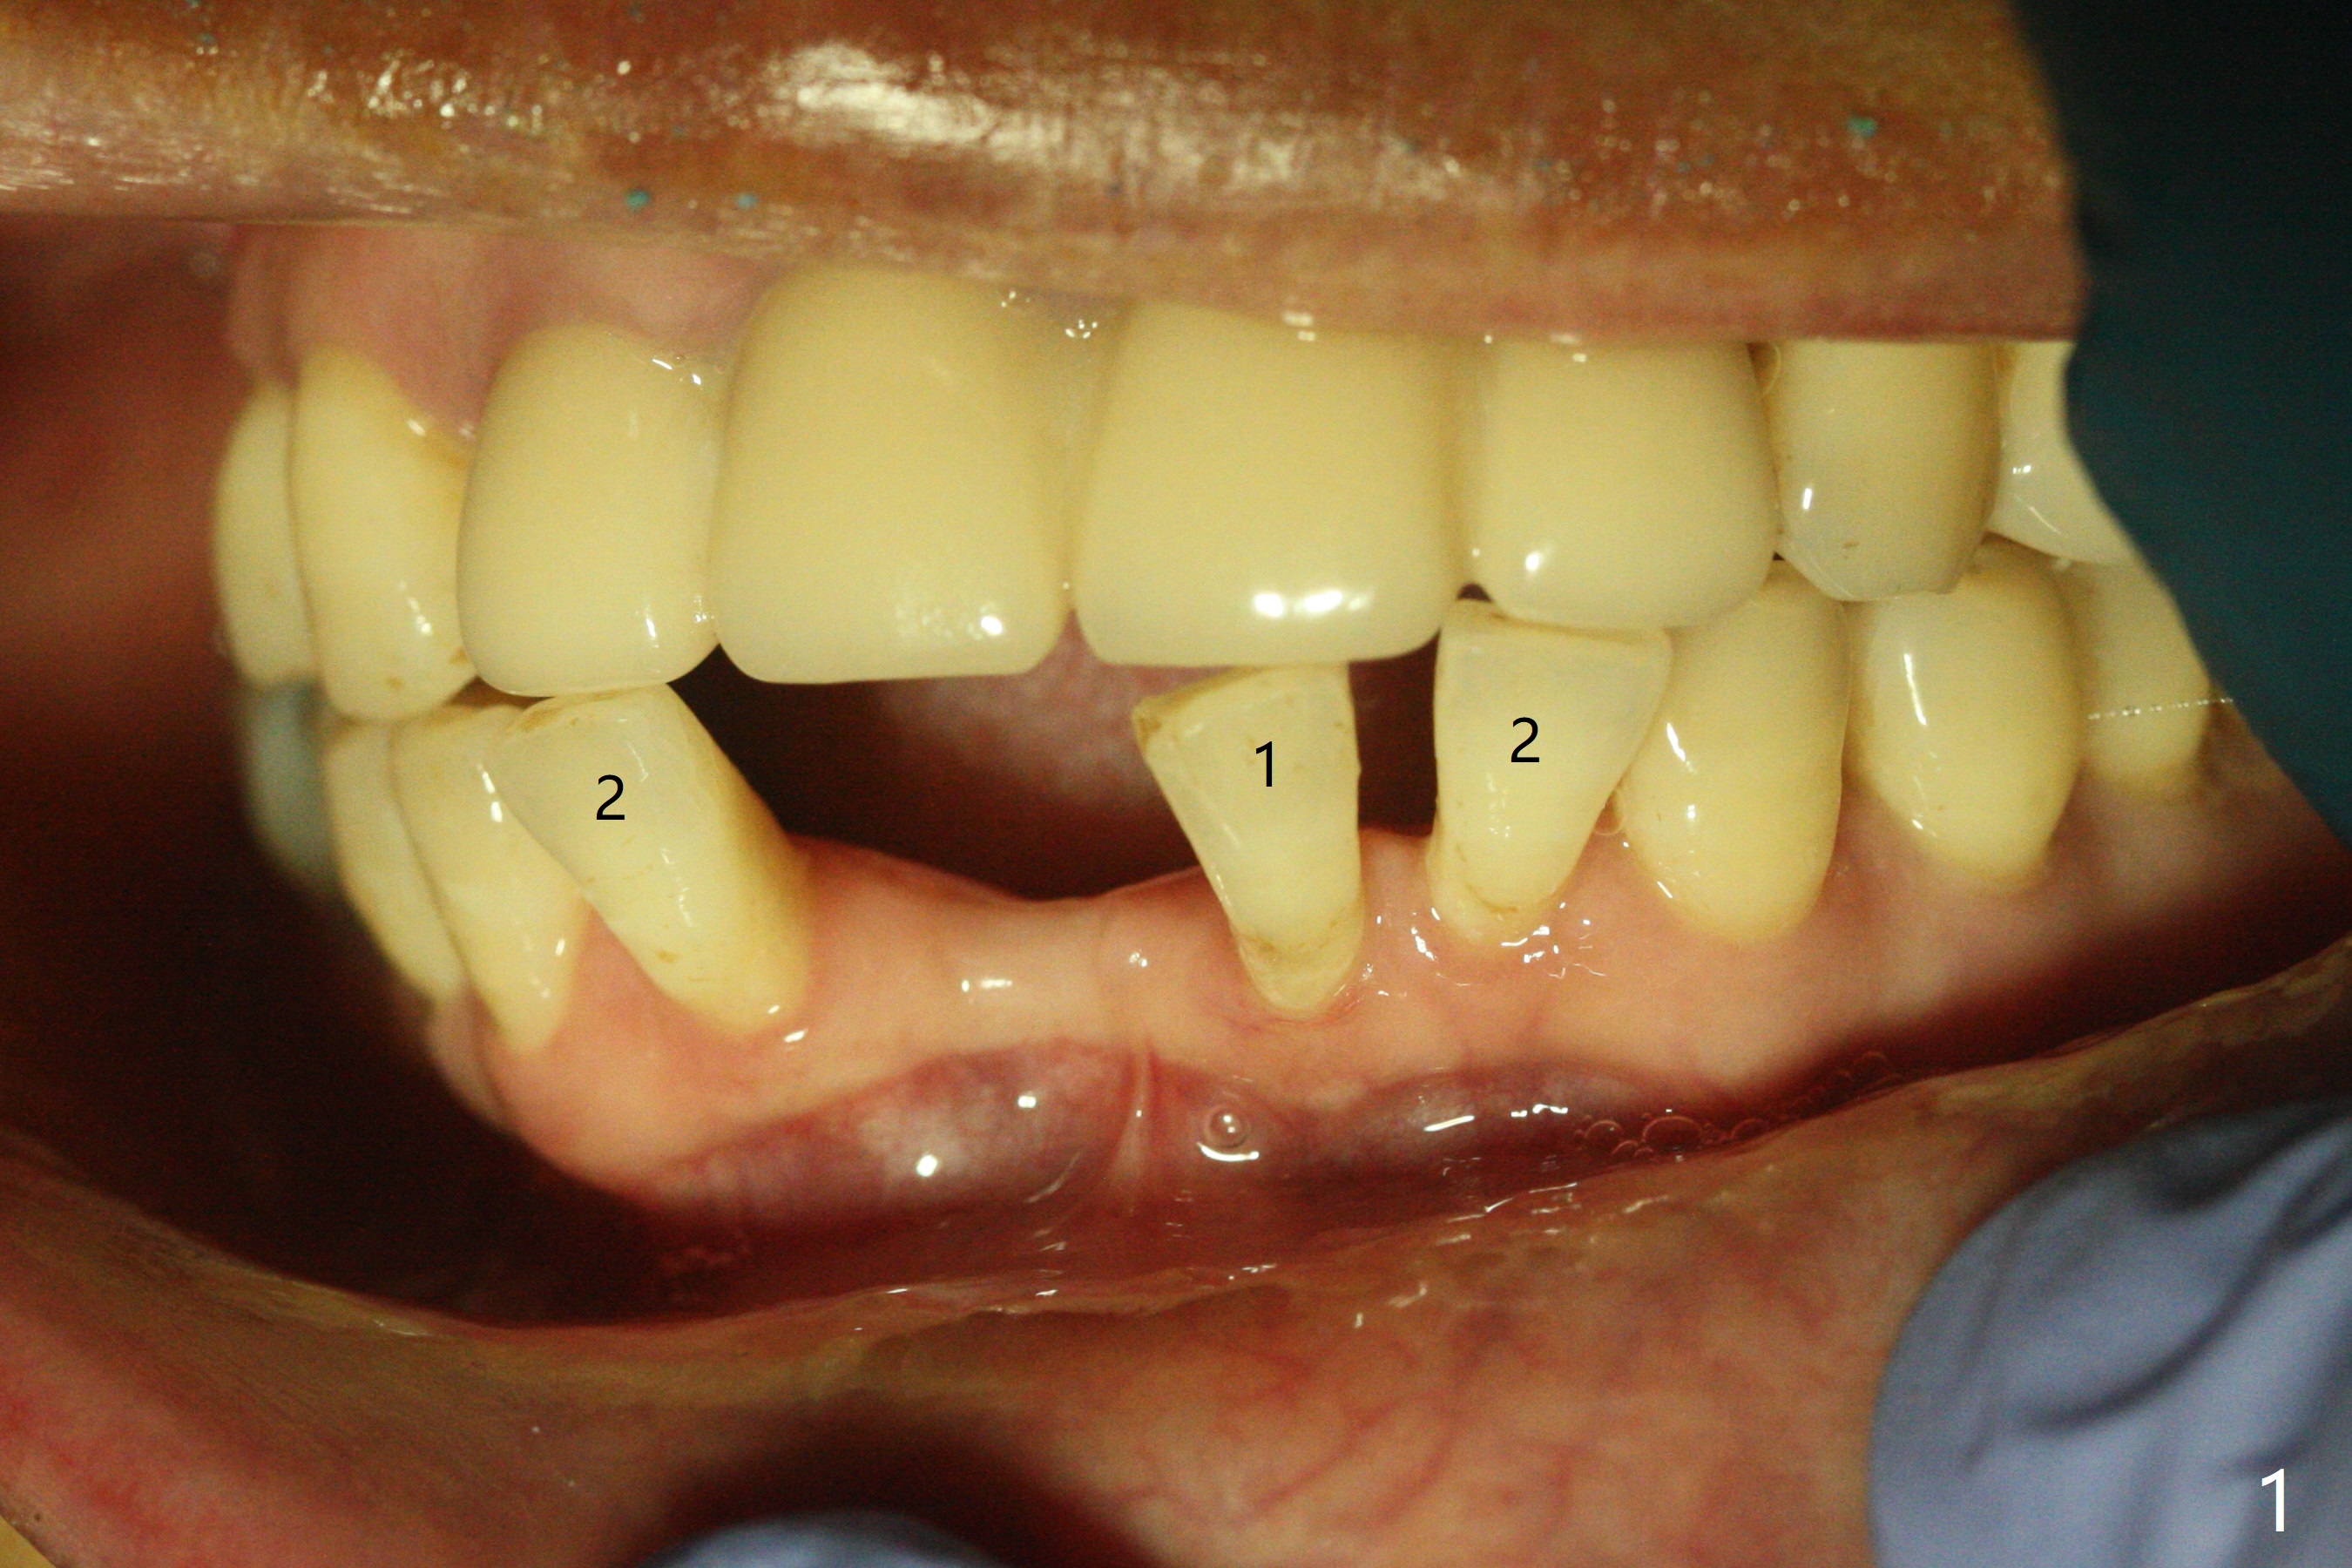

56岁女十分恐惧治疗,缺失右下1,其余切牙由于骨质吸收颊侧移位(图一:1,2),但是她不愿意拔除,同意右下1种植,牙周骨手术,植骨;植体整合后作为支抗,矫正移位下门牙。为了防止忘记舌侧瓣分离,先做舌侧切口(图二),然后颊侧瓣松弛分离(图三),包括使用前牙隧道刀(图四)切断颊侧骨膜,松弛到颊侧瓣能向舌侧牵拉3-4毫米(图五),舌侧瓣骨膜下广泛,深部分离(好像不能切断骨膜,图六),放置导板,磨平狭窄的牙槽嵴(图七:O(osteotomy)),植入2.5x12(4)毫米一段式植体(图八:故意舌侧植入,以便以后矫正),在颊侧骨板打多个出血洞(图八:箭头),然后把在平的器皿上形成的粘性骨板(sticky bone,图九),放置于植体和移位切牙周围(图十),接着使用消毒过的橡皮障punch(图十一(纸头相当于PRF膜;事先给助手示范))在三个PRF膜(图十二)打洞,套在植体和门牙上(图十三: 箭头),防止膜(图十四)和骨块(图十五,十六:*)移位,最后还必须使用最原始方法牙周敷料保护伤口(图十七)。术后9天,舌侧牙周敷料脱落,伤口稍微裂开(图十八)。术后18天撤除敷料,伤口裂开处有新鲜肉芽组织生长(图十九(*:下面是填入的骨粉,将是增宽的牙槽嵴(如果你是乐观主义者)),二十)。病人十分感激我们帮助她度过难关。她的确有sleep apnea,否定tongue thrust。术后三个月植体周围没有明显骨质吸收(图二十一至二十三),左下1,2轻度反合(图二十四),植体周围软组织健康(图二十五),5-5安置矫正器(图二十六,二十七,12 niti)。一周后下切牙向舌侧移动(图二十八),左下1,2反合纠正(图二十九)。再一周变化不大(图三十),植牙圈有些松动,两周后将重做临时牙冠,槽往舌侧移动。结果病人提前回来,植牙槽舌侧移位。一周后右下2不适(图三十一),尝试近中牵引(图三十二)。